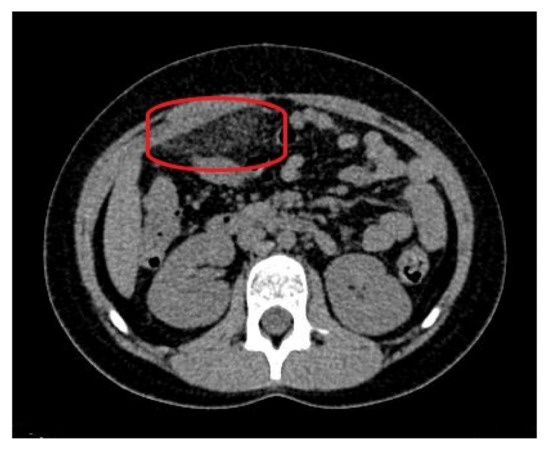

As the ultrasound examination was inconclusive, a team of doctors consisting of a pediatric surgeon, a pediatric gastrologist and a radiologist decided to expand the diagnostics with a non-contrast CT of the abdomen and pelvis. The examination showed a focal area of fat stranding, measuring 58 × 20 mm (transverse dimension), in the right epigastrium, anterior to the site of the gastric connection to the duodenum, along with small-banded thickenings along both flanks and in the lower abdomen. In addition, there was no free gas in the abdominal or pelvic cavities and the appendix presented with no signs of inflammation (Figure 3).

Figure 3. The computed tomography of the abdomen on admission: fat stranding in the right epigastrium (marked with a red ellipse).